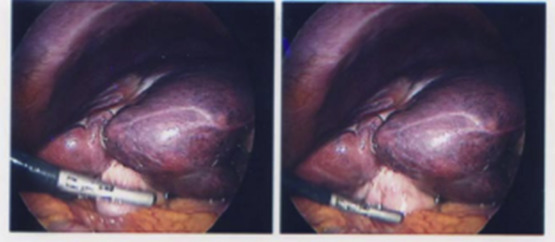

All patients in our series had extensive preprocedural work up with clinical and radiological screening. Review of single-photon emission computed tomography imaging performed following macroaggregated albumin workup and post sphere implantation did not reveal increased radioisotope uptake in the gallbladder although such uptake is difficult to perceive in a hollow viscus such as the gallbladder. In only one case (Case 3) was there intense contrast enhancement of the gallbladder on angiography during the implantation that raised the possibility that the patient might be at risk of radioembolization related cholecystitis. All patients had adequate pretreatment hematologic, hepatic, and renal function. Careful angiographic assessment of the arterial anatomy was carried out in all patients and embolization of any aberrant vessels or any prominent cystic artery as was performed in Case 2. All our patients presented with abdominal pain between 1 month and 4 months of sphere implantation. All patients required cholecystectomy as the symptoms did not resolve with analgesia and antibiotics. Intraoperatively, the gallbladders were found to be fibrotic and contracted (Figure 1). The temporal relationship with radioembolization, fibrosis and inflammation and the presence of microspheres within the gallbladder wall strongly suggested radiation induced cholecystitis (Figure 2). The patients in this series had thick walled contracted gallbladders and livers were stiff due to the effects of chemotherapy and 90Y microspheres making the cholecystectomy particularly difficult.

Intraoperative laparoscopic view of gallbladder.

Figure 1.